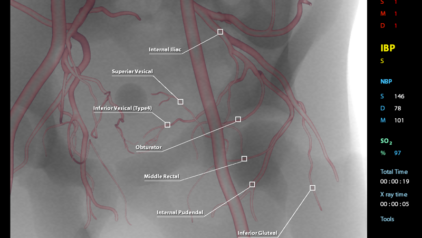

This module aims to enhance technical and procedural skills for the challenging Prostatic Artery Embolization technique, used to treat benign prostatic hyperplasia. The embolization is performed by injecting spherical and non-spherical particles of various sizes.

- Become proficient in prostatic artery embolization techniques (PerFecTED and standard)

- Identify the prostatic artery and surrounding vessels in common and rare anatomical variants